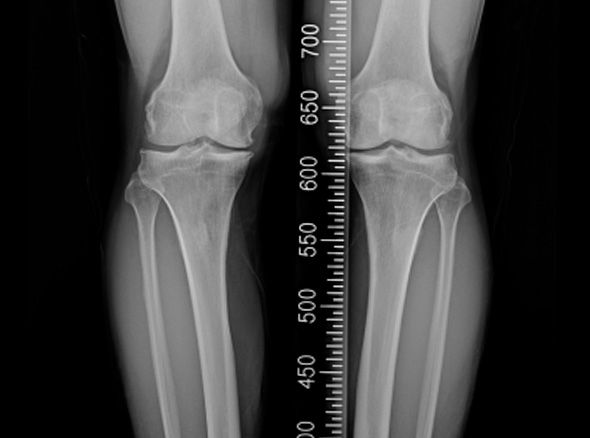

한국인의 대부분에게서 무릎 내측에 무릎 관절염이 발생됩니다.

관절염의 수술적 치료로는 인공관절 수술이 가장 흔하지만, 인공관절 수술을 할 만큼

연골 손상이 심하지 않다면 내측으로 치우친 체중 부하를 정상적인 외측 관절로

이동시키는 ‘무릎관절 교정 절골술’을 시행합니다.

관절내시경을 이용하여 연골재생이나 연골판에 필요한 치료를 시행한 후 경골(무릎 아래 뼈)의 근위부의

계획한 위치까지 절골을 시행한 후 뼈의 탄성을 이용하여 벌립니다. 그리고 금속판과 나사로 고정하여

수술 전 계획했던 X자형 또는 1자형 다리를 만들고 빈 공간에 뼈를 이식하여 골유합을 유도합니다.